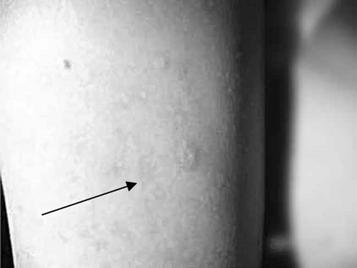

Рисунок 11 - Гипертрофические липодистрофии (липогипертрофии)

ПРИЛОЖЕНИЕ Н

Рисунок 12 - Липоатрофии в области плеча